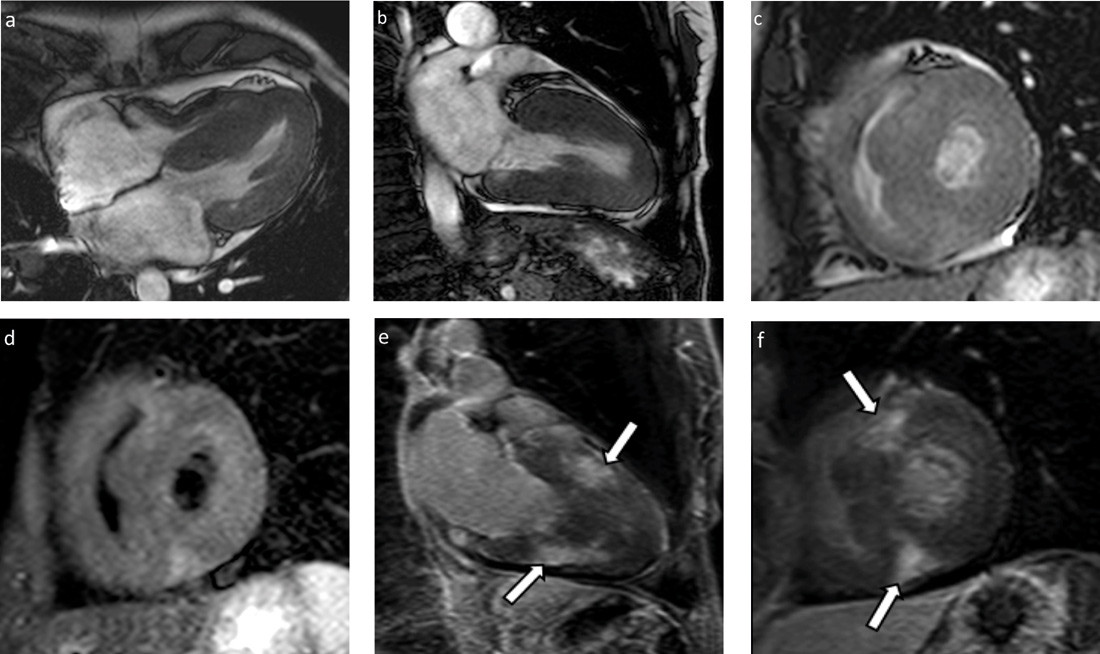

MR-undersøkelsen ble gjennomført med funksjonsserier i tre plan, T2-vektet kortakse før og T1-vektet serie i kort- og langakse etter intravenøs gadoliniumkontrast (fig 3). Undersøkelsen bekreftet ujevn myokardfortykkelse i begge ventrikler, spesielt fremtredende i septum. Begge atrier var lett forstørret, og det ble påvist lettgradige mitral- og trikuspidalinsuffisienser, uten hemodynamisk betydning. Ejeksjonsfraksjonen ble estimert til 65 % (> 60 %), og venstre ventrikkels myokardmasse ble beregnet til 135 g (70 – 180 g). Det ble påvist flekkevise, store områder med kontrastoppladning (late gadolinium enhancement, LGE), mest uttalt anteroseptalt og inferiørt i venstre ventrikkels myokard. Områder med kontrastoppladning var lokalisert sentralt i myokard eller transmuralt, men ikke subendokardialt. I tillegg ble det funnet noe perikardvæske samt flere forstørrede glandler, særlig i høyre hilusregion.